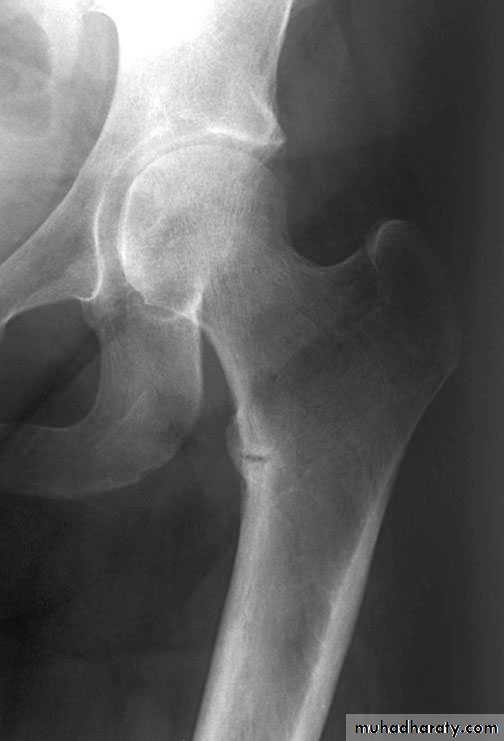

AP view looser’s zone

frogleg view looser’s zone

Osteomalacia: Bone scanRadiographic features

1-Generalized osteopenia2-Looser's zones (pseudofractures):

cortical stress fractures filled with

poorly mineralized osteoid tissue.

* Milkman's syndrome: osteomalacia

with many Looser's zones

Typical location of Looser's zones

(often symmetrical)

Axillary margin of scapula

Inner margin of femoral neck

Rib

Pubic, ischial rami

* Osteomalacia may be indistinguishable from osteoporosis; however, Looser's

zones are a reliable differentiating feature.